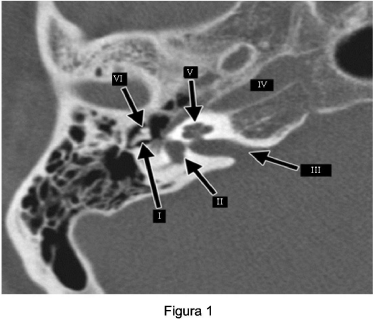

A tomografia computadorizada (TC) tem papel fundamental no estudo do aparelho auditivo, uma vez que, através dela podem ser avaliadas estruturas não visualizadas no exame com otoscópio. Em situações clínicas diversas, o diagnóstico, por meio desse exame, mostra-se limitado, sendo fundamental o exame de imagem associado às reformatações digitais. Observe a figura 1 para responder a questão.

Com relação à Figura 1 é correto afirmar: